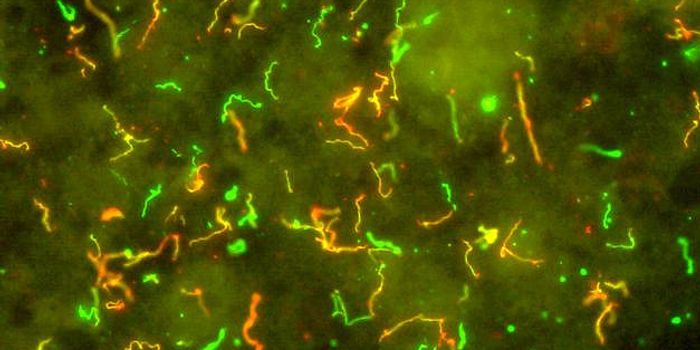

AUG 25, 2016MicrobiologyResearchers have learned more about how Lyme disease invades the body, and will publish their findings September 6 in Ce ...

-